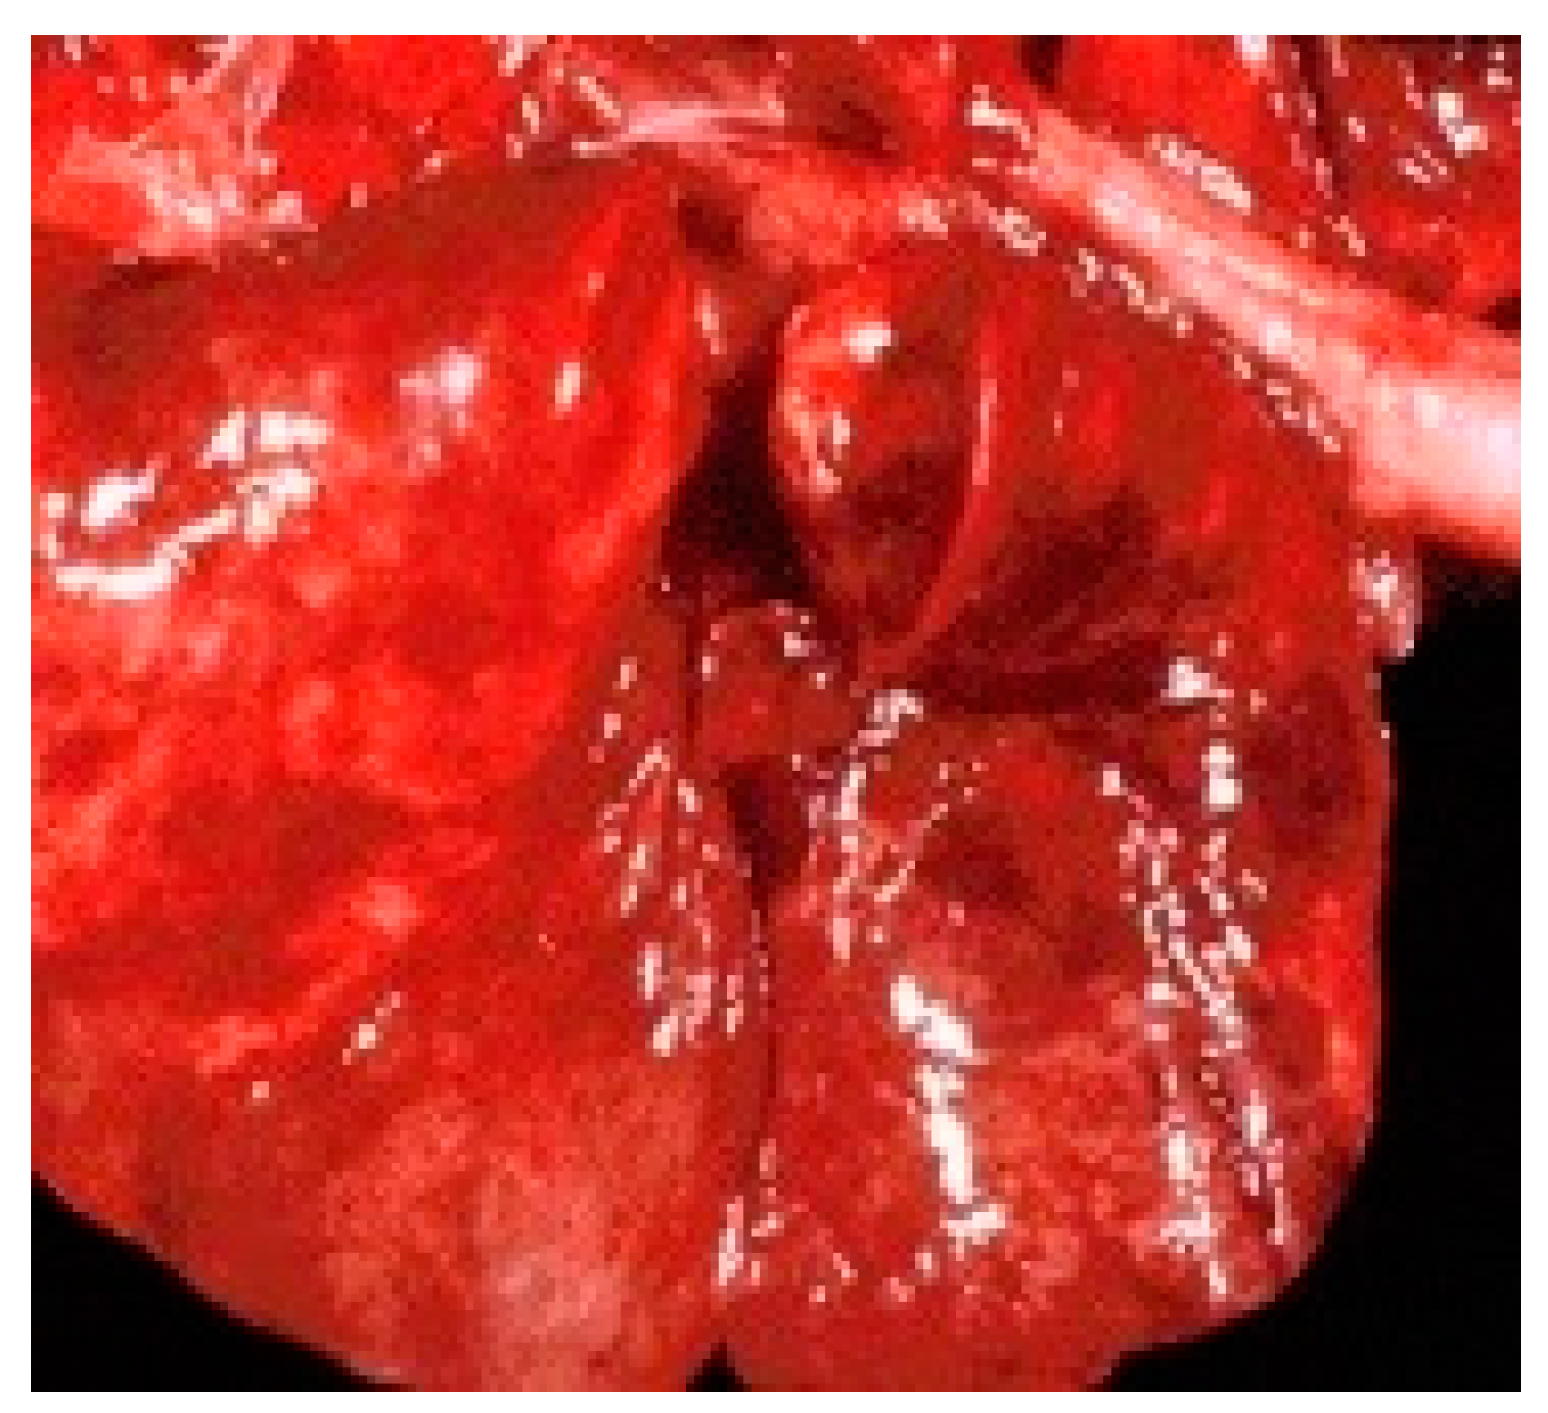

3.3. Necropsy exam.

3.6. Immunohistochemical / histopathological examination